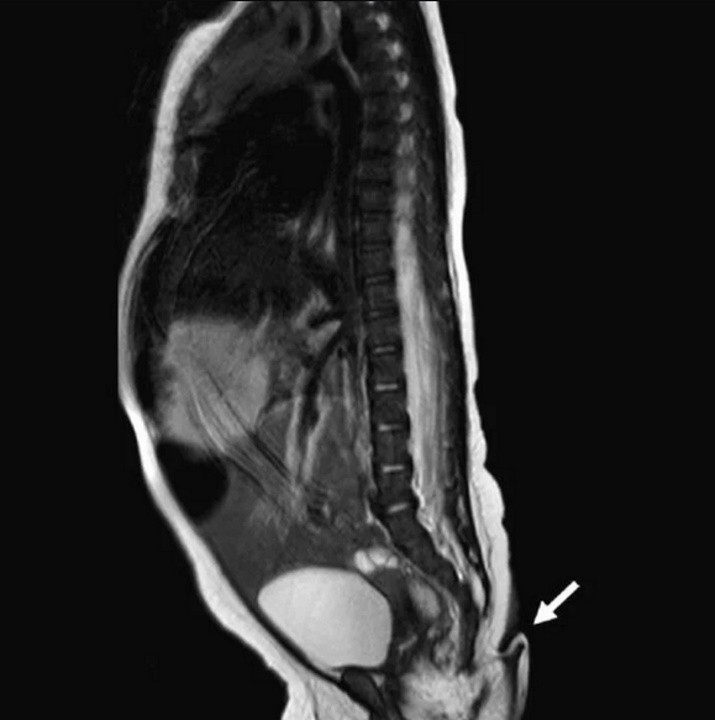

Cuando los especialistas examinaron la cola, notaron que salía del final de su coxis y que tenía una base ligeramente corrida a la izquierda. Además, indicaron que la podía mover sin dolor, pero que tenía sensibilidad en ella pues cuando la pincharon con una aguja se puso a llorar. Tras varios análisis, notaron de que la bebé está sana; y que los resultados de las pruebas cerebrales, cardíacas, auditivas y urinarias eran normales, indicó el citado medio. Existen dos tipos de "colas humanas". Por un lado, las "pseudocolas", que son crecimientos que se asemejan a una cola pero que se originan en la columna vertebral o en tumores, es decir, son causadas por alguna enfermedad subyacente. Por otro lado, están las "colas verdaderas", que son las que contienen músculos, vasos sanguíneos y nervios. En este caso, los médicos notaron que la estructura en forma de cola estaba cubierta de pelo y piel. Luego, realizaron una radiografía lumbosacra, una prueba de imagen que ayuda al médico a ver la anatomía de la parte inferior de la espalda, pero no encontraron evidencia de anomalías o estructuras óseas dentro de la cola. Esto significa que la cola no era una cola sin función, en el sentido de un apéndice que con el tiempo ha perdido cualquier uso en el cuerpo, sino una "verdadera cola", una estructura benigna compuesta de tejido conjuntivo, músculo y nervios. Tras dos meses, los médicos volvieron a examinar a la pequeña y reconocieron que la cola había crecido alrededor de 1 centímetro. Fue por eso que determinaron que debían operársela, lo cual no presentó ningún tipo de complicación.